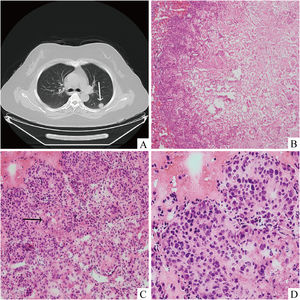

Thoracic CT (A) scan displayed an irregular mass with superficial lobulation and burr sign located at the dorsal segment of the left lung lower lobe (white arrow). (B) Intraoperative consultaion revealed that the centre of the nodule was hypocellular and the peripheral areas consisted of abundant tumour cells (Hematoxylin and eosin stain, 40 ×). Epithelioid tumour cells with nuclear deviation were arranged in solid sheets with (C) necrosis (Hematoxylin and eosin stain, 200 ×) (black arrow) and (D) marked atypia (Hematoxylin and eosin stain, 400 ×).

A 44-year-old female patient presented to our respiratory clinic with a pulmonary nodule detected upon physical examination. The patient had no history of smoking or lung disease. Thoracic computed tomography (CT) revealed an irregular mass in the dorsal segment of the left lung lower lobe with shallow lobulation and spiculation, measuring approximately 18 × 15 mm (Fig. 1A). The patient underwent a lobectomy, and upon intraoperative consultation, the tumour appeared greyish, medium-textured, poorly demarcated, and immediately adjacent to the pleura with pleural indentation. The mass centre was hypocellular and the peripheral areas were hypercellular (Fig. 1B), The peripheral tumour cells displayed a solid sheet growth pattern with necrosis (Fig. 1C). The neoplastic cells were eosinophilic epithelioid, with abundant cytoplasm, nuclear deviation, and clear nuclear pleomorphism (Fig. 1D). After intraoperative consultation, the condition was diagnosed as lung adenocarcinoma. Permanent section analysis showed results similar to those of the frozen sectioned material. Nevertheless, tumour cells grew primarily within the alveolar space; extensive necrosis and focal parietal pleural invasion were observed (Fig. 2A–C). Eosinophilic epithelioid tumour cells pervaded in a transparent matrix with obvious atypia and mitotic figures (Fig. 2D and E). Intracytoplasmic vacuolisation was discovered in some tumour cells, indicating primitive angiogenesis. Additionally, some of these tumour cells can be observed with intracytoplasmic lumen and erythrocyte inside, indicating their vascular nature (Fig. 2F). Immunohistochemically, diffuse neoplasm cells stained for CD34 (Fig. 3A) and ERG (Fig. 3B) were observed, whereas the keratin marker AE1/AE3 (Fig. 3C) and TTF-1 (Fig. 3D) were negative. Based on these radiological, histological and immunohistochemical findings, a diagnosis of malignant pulmonary epithelioid hemangioendothelioma was established. After surgery, the patient underwent complementary radiotherapy. No tumour recurrence or metastasis had occurred at the six-month postoperative follow-up.